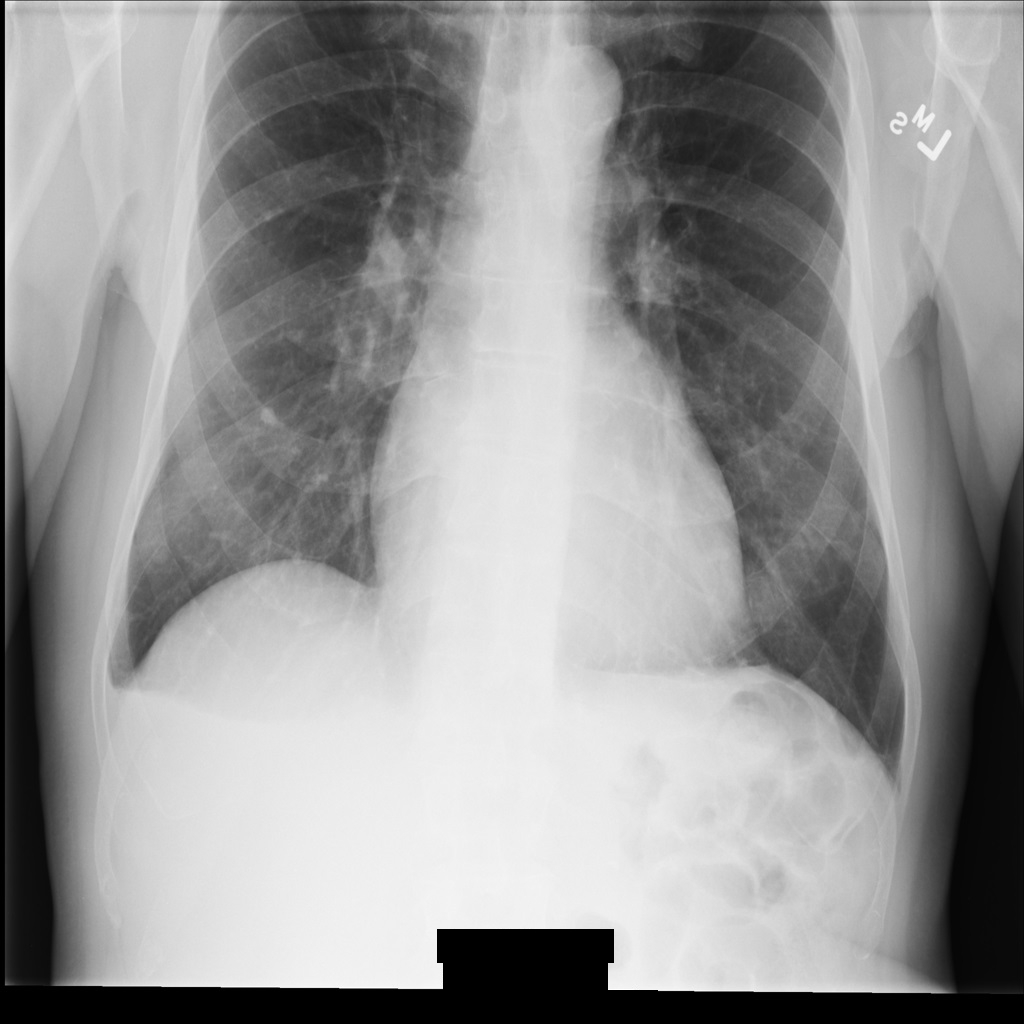

Depois de remover a identificação da imagem com REDACT_ALL_TEXT, a imagem

tem o seguinte aspeto. Repare que todo o texto incorporado na parte inferior da imagem foi ocultado.